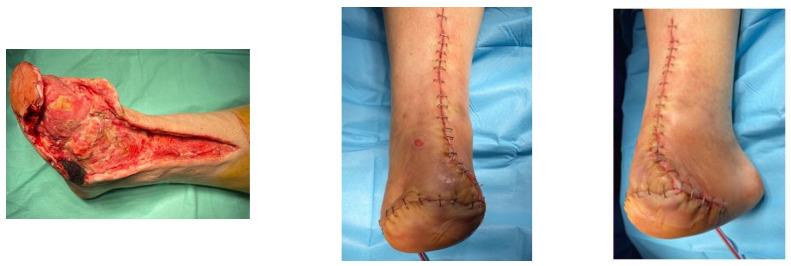

: Revascularization based on the angiosome concept (AC) is a controversial subject because there is currently no clear evidence of its efficacy, due to the heterogeneity of patients (multiple and diverse risk factors and comorbidities, multiple variations in the affected angiosomes). Choke vessels change the paradigm of the AC, and the presence or absence of the plantar arch directly affects the course of targeted revascularization. The aim of this study was to evaluate the effect of revascularization based on the AC in diabetic patients with chronic limb-threatening ischemia (CLTI). This retrospective analysis included 51 patients (40 men, 11 women), with a mean age of 69 years (66-72) and a total of 51 limbs, who presented with Rutherford 5-6 CLTI, before and after having undergone a drug-coated balloon angioplasty (8 patients) or plain balloon angioplasty (43). Between November 2018 and November 2019, all patients underwent below-the-knee balloon angioplasties and were followed up for an average of 12 months. The alteration of microcirculation was compared between directly and indirectly revascularized angiosomes. The study assessed clinical findings and patient outcomes, with follow-up investigations, comparing wound healing rates between the different revascularization methods. Patient records and periprocedural leg digital subtraction angiographies (DSA) were analyzed. Differences in outcomes after direct revascularization and indirect percutaneous transluminal angioplasty (PTa) were examined using Cox proportional hazards analysis, with the following endpoints: ulcer healing, limb salvage, and also amputation-free survival. Direct blood flow to the angiosome supplying the ulcer area was achieved in 38 legs, in contrast to 13 legs with indirect revascularization. Among the cases, there were 39 lesions in the anterior tibial artery (ATA), 42 lesions in the posterior tibial artery (PTA), and 8 lesions in the peroneal artery (PA). According to a Cox proportional hazards analysis, having fewer than three (<3) affected angiosomes (HR 0.49, 95% CI 0.19-1.25, = 0.136) was associated with improved wound healing. Conversely, wound healing outcomes were least favorable after indirect angioplasty ( = 0.206). When adjusting the Cox proportional hazard analysis for the number of affected angiosomes, it was found that direct drug-coated angioplasty resulted in the most favorable wound healing ( = 0.091). At the 1-year follow-up, the major amputation rate was 17.7%, and, according to a Cox proportional hazards analysis, atrial fibrillation (HR 0.85, 95% CI 0.42-1.69, = 0.637), hemodialysis (HR 1.26, 95% CI 0.39-4.04, = 0.699), and number of affected angiosomes > 3 (HR 0.94, 95% CI 0.63-1.39, = 0.748) were significantly associated with poor leg salvage. Additionally, direct endovascular revascularization was associated with a lower rate of major amputation compared to indirect angioplasty (HR 1.09, 95% CI 0.34-3.50, = 0.884). Observing the angiosomes concept in decision-making appears to result in improved rates of arterial ulcer healing and leg salvage, particularly in targeted drug-coated balloon angioplasty for diabetic critical limb ischemia, where multiple angiosomes are typically affected.

基于血管体概念(AC)的血运重建是一个有争议的话题,因为目前尚无明确证据证明其疗效,这是由于患者存在异质性(多种不同的风险因素和合并症,受累血管体存在多种变异)。窒息血管改变了AC的模式,足底弓的存在与否直接影响靶向血运重建的进程。本研究的目的是评估基于AC的血运重建对慢性肢体威胁性缺血(CLTI)糖尿病患者的影响。这项回顾性分析纳入了51例患者(40例男性,11例女性),平均年龄69岁(66 - 72岁),共51条肢体,这些患者在接受药物涂层球囊血管成形术(8例)或普通球囊血管成形术(43例)前后均表现为卢瑟福5 - 6级CLTI。在2018年11月至2019年11月期间,所有患者均接受了膝下球囊血管成形术,并平均随访12个月。比较了直接和间接血运重建血管体之间的微循环变化。该研究评估了临床发现和患者预后,并通过随访调查比较了不同血运重建方法之间的伤口愈合率。分析了患者记录和围手术期腿部数字减影血管造影(DSA)。使用Cox比例风险分析检查直接血运重建和间接经皮腔内血管成形术(PTa)后结局的差异,终点如下:溃疡愈合、肢体挽救以及无截肢生存率。38条腿实现了向供应溃疡区域的血管体的直接血流,相比之下,13条腿为间接血运重建。在这些病例中,胫前动脉(ATA)有39处病变,胫后动脉(PTA)有42处病变,腓动脉(PA)有8处病变。根据Cox比例风险分析,受累血管体少于三个(<3)(HR 0.49,95%CI 0.19 - 1.25,P = 0.136)与伤口愈合改善相关。相反,间接血管成形术后伤口愈合结局最不理想(P = 0.206)。在对受累血管体数量进行Cox比例风险分析调整后,发现直接药物涂层血管成形术导致最有利的伤口愈合(P = 0.091)。在1年随访时,大截肢率为17.7%,根据Cox比例风险分析,心房颤动(HR 0.85,95%CI 0.42 - 1.69,P = 0.637)、血液透析(HR 1.26,95%CI 0.39 - 4.04,P = 0.699)以及受累血管体数量>3(HR 0.94,95%CI 0.63 - 1.39,P = 0.748)与肢体挽救不佳显著相关。此外,与间接血管成形术相比,直接血管内血运重建与较低的大截肢率相关(HR 1.09, 95%CI 0.34 - 3.50, P = 0.884)。在决策过程中遵循血管体概念似乎能提高动脉溃疡愈合率和肢体挽救率,特别是在针对糖尿病严重肢体缺血的靶向药物涂层球囊血管成形术中,此时多个血管体通常会受累。